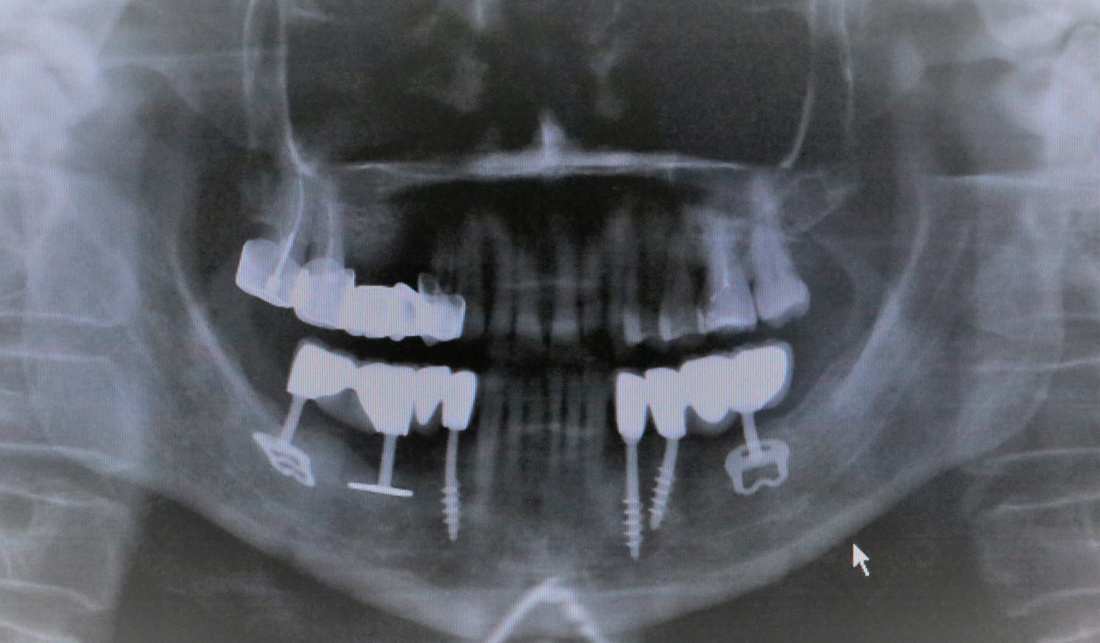

Не нужно расстраиваться! Базальная имплантация — это поправимо.